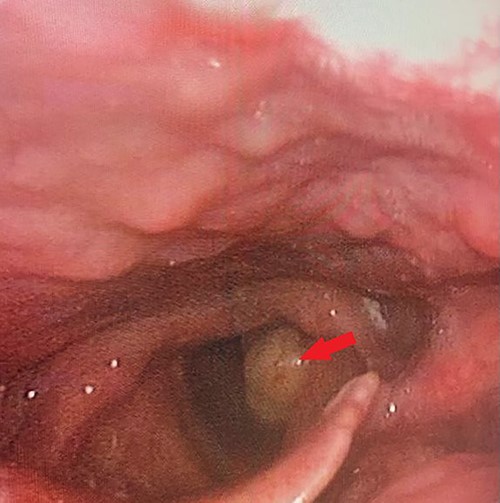

Flexible laryngoscopic examination of the larynx, showing left sided polypoidal mass.

A thorough otorhinolaryngology examination was done and revealed clear oral cavity as well as normal dental health condition. On flexible laryngoscopic examination, a 2 × 1-cm yellowish polypoidal mass covering left vocal cord was found with mild signs of reflux (Fig. 1).